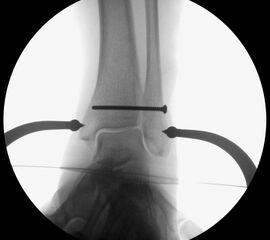

Die eigentliche Reposition der Syndesmose erfolgt mittels einer Repositionszange über dem Malleolus medialis und lateralis, entlang der Achse des oberen Sprunggelenkes und wird nach Reposition in anatomischer Stellung fixiert 52. Dabei ist auf eine Neutralstellung im oberen Sprunggelenk zu achten. Die temporäre Fixierung des DTFG kann mittels Schraube(n) oder einem dynamischen System (Suture Button - z.B. Tight-Rope, Fa. Arthrex™) erfolgen. Bei der Fixierung mittels Schraube können eine oder zwei Schrauben von 3,5-4,5 mm Stärke, tri- oder quadricortical, verwendet werden 53. Dies werden am posterolateralen Rand der Fibula in leicht aufsteigender Technik (30°), circa 2 cm und 3,5 cm oberhalb der tibiotalaren Gelenkfläche, parallel zur OSG-Achse nach entsprechendem Vorbohren eingebracht. Eine Schraubenpositionierung 2 cm oberhalb der tibiotalaren Gelenkfläche konnte in biomechanischen Untersuchungen eine bessere biomechanische Stabilität des DTFG gewährleisten als eine Positionierung der Schraube weiter proximal 54. Keinen Vorteil gegenüber tricortical eingebrachten Stellschrauben wiesen dagegen Schrauben auf, welche vier Corticalices fassen 55. Ob eine Entfernung der Syndesmosenstellschraube sinnvoll ist oder nicht, ist bist heute Bestandteil der internationalen Diskussion 56. Wir Entfernen Stellschrauben nach ca. 6 Wochen bei erhaltenem PITFL, sind alle Syndesmosenbänder verletzt, wird die Stellschraube 8 Wochen belassen.

Alternativ können verschiedene dynamische Systeme verwendet werden. Hierbei erfolgt, wie oben beschrieben, die Reposition der DTFG mittels Repositionszange. Anschließend wird in derselben Technik, wie bei der Syndesmosenstellschraube, quadricortical vorgebohrt. Hierauf wird durch den vorgebohrten Tunnel das Fadensystem (Suture-Button) von lateral nach medial durchgezogen und medial transkutan über die an dem Fadenende befestigte Nadel ausgeleitet. Über das speziell angebrachte Fadensystem lässt sich der mediale Button parallel zur medialen Kortikalis ausrichten und durch Zug am lateralen Faden an die medialen Tibiakortikalis heranzuiehen. Anschließend wird durch Anspannen der lateralen Fadenenden der laterale Button auf der Fibula platziert. Nach Erreichen der gewünschten Festigkeit und Reposition des DTFG werden die lateralen Fadenenden verknotet und abgeschnitten. Die medialen Fadenenden werden ebenfalls entfernt. Ziel des dynamischen Stabilisierungsverfahren ist eine physiologische Bewegung im DTFG zu ermöglichen bei gleichzeitiger Sicherung der Gelenkstabilität 57. Eine Materialentfernung ist bei diesen Systemen nicht zwingend erforderlich. Bei der ersten Generation der Suture-Button-Systeme sind Hautirritationen und Wundheilungsstörungen in ca. 10% der Fälle beschrieben. Ob diese durch die inzwischen erhältlichen knotenlosen Systeme vollständig verhindert werden, ist Gegenstand aktueller Untersuchungen.